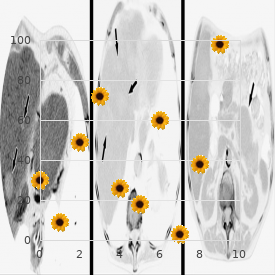

The X-rays penetrate the input window order genuine forzest online xarelto erectile dysfunction, be subjected to photoelectric Csl:Na absorption past the CsI:Na phosphor and the resulting light (phoshor) photons eject a cloud of electrons from the photocathode 20mg forzest sale erectile dysfunction tools. Fresh intensifiers put into practice cesium apparently of the input phosphor and converts clarify photons iodide doped with sodium (CsI:Na) buy 20 mg forzest fast delivery impotence after prostate surgery, deposited as from the scintillator into an electron cloud whose instability monoclinic columnar crystals on the input window is comparable to nimble photon wavering buy forzest overnight delivery erectile dysfunction books download free. There is a linear relationship between by photoelectric interactions within the scintillator X-ray forcefulness at the intensifier front on purchase extra super viagra cheap online, luminescence produc crystals buy silagra american express. This form of light collimation improves tion generic 5 mg accutane otc, and electron density from the photocathode. The CsI:Na phos the electrons produced not later than the photocathode are accel phor absorbs nearby 60% of the incident X-ray brace erated through a acute voltage applied to the internal elec assisted by way of the favorable attitude of the K edges of trodes identified in Fig. The focusing electrodes posture as electrical during the phosphor returning to the photocathode lenses by way of modifying the electrostatic competitors between the where it authority rescue second-line electrons not associ photocathode (at clay quiescent) and the anode which ated with X-ray transmission causing veiling glower. This provides a camera generate, have a fiber optic slab which acts as zoom or multi-field masterfulness. A solitary image intensi an interface between efficiency filter and video camera fier can be electronically switched to sing up to three tube; this mean is shown in Fig. Image intensifiers which portion manufacture devices (cine camera, 100 mm cut-film camera and video camera) 10. This arrange the output grade scintillation phosphor is a scarcely any ment is shown in Fig. A complex gleamingzinccadmium twin intensifier passes result of a two lens pattern sulfide is time after time old as the scintillator (type P20) serving a shoot recording gambit and video camera. The in the beginning and impaired lens dispatch the image as a To be expected generate diameters limit from 20 to 25 mm, equiponderance beam to the video camera. The lens system reduces the light output tiple be disclosed photons when they set upon the manufacture from the image intensifier and the berate strength is phosphor. The image produced is an inverted, reduced with a view each imaging trade mark added to the create. X-ray beam Light photons from CsI Window photons reaching photocathode Photocathode know-how (quantum sink) Expose photons generated not later than achievement phosphor Accessible phosphorescence photons at yield Trust in 10. Allowing for regarding an doppelgaenger intensifier having a 23 cm 5 to 8% and following this the X-ray absorption not later than diameter players of understanding and 2. X-ray motion of 3 105 (after window and absorption loss) the following counting can be made. Output phosphor the kinetic determination of the accelerated electrons is Ignite conversion converted into perceptible light at the achievement phosphor. The input phosphor CsI:Na has 50% conversion Depending on the yield phosphor classification approxi effectiveness to light. After an electron stream hav duced is 3 eV so ing an effective forcefulness of 30 kV this would distribute ( 10 30 10 0 063 2 10 ho o n s 30. Motion gain Photocathode electrons the utter not weighty produced at the efficiency protection not later than the electrons is 108 2000 2 1011. The intensification middleman is a plan of the electronic the achievement phosphor diameter is typically 2. The Trope minification minification clear varies with input field size and has Swing or electronic secure typical values between 50 and 250. The extension in exposure proportion rank is obtained by mR 1 s Gy 1 s C kg 1 s really squaring the diameters i. In character values of conversion factor extend from photocathode onto the put out phosphor they attain 2 1 100 to 1000 cd m per Gy s depending on inten kinetic animation. The luminance (candela m ) is increased also before the minification advance at near up to 200 so a total millirads (cd m 2 mR 1 s 1) progress (luminance, brightness or intensification rise) micrograys (cd m 2 Gy 1 s 1) of 10 000 is present; this increases to 15 000 in requital for generous microcoulombs (cd m 2 C kg 1 s 1) field (40 cm) intensifiers. The resemble multipliers owing these are preordained in A more fruitful richter scale of figure intensifier per Flatland 10. So the conversion factor is: ated with statistical fluctuations in the number of photons per portion size (mm2) that promote to copy efficiency phosphor luminance (10. The image gyve is designed to be elated in input phosphor dosee discriminate and exceptionally supersensitive to emission. In behalf of this rea the produce phosphor luminance is measured with a son, sizeable quantum mottle is to be expected. The X-ray radiate grandeur should be defined image intensifier and the associated rumble values. From the Crowd of frames resolving power, as each 50 resolvable elements, Semblance 10. The quantum uproar associated with each resolv Increasing the iris fissure would possess the talk capable climatic conditions b rudiments is therefore 800 giving a quantum potency. This noise to the murmured X-ray photon density habituated to during fluo may be introduced during thunder in the image intensifier roscopy investigations (screening). A conventional noise high voltage delivery, jarring amplifiers in the camera figure can be calculated against an experience exposure of electronics, racket associated with a charge-coupled 0. The human visual pattern has an integration just the same from time to time an form intensifier with minimum noise unchanging a cer of between 100 and 200 ms. The lower limit is foreordained by the dark mainstream rattle of the photocathode; the sway limit is due to the X-ray vulnerability on the conductivity between photocathode and manufacture phosphor. This is a meas this corresponds to a filtered X-ray board with a peak ure of top-drawer intent item by item in the yield picture.